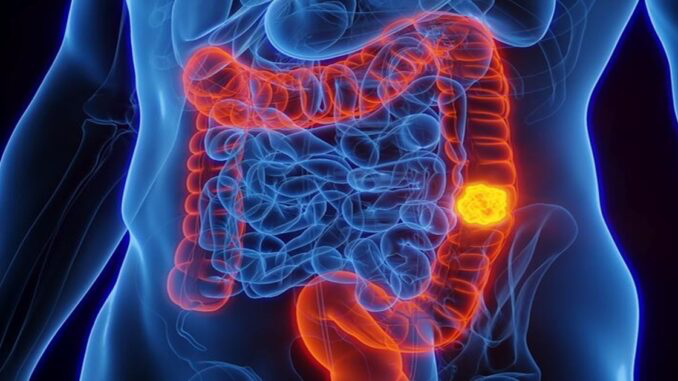

Dickdarmkrebs ist eine der häufigsten Erkrankungen, die die menschliche Bevölkerung betrifft, wobei seine Symptome oft bis in fortgeschrittene Stadien unsichtbar sind. Obwohl viele Menschen Gespräche über den Stuhlgang meiden, können gerade Veränderungen in dessen Konsistenz und Form auf ernstere Gesundheitsprobleme hinweisen, einschließlich Krebs. Wie erkennt man also, wann man medizinische Hilfe aufsuchen sollte?

Ärzte warnen, dass lockerer und schmaler Stuhl ein Zeichen mehrerer Probleme sein kann, einschließlich Dickdarmkrebs. Diese Art von Stuhl ist oft dünn wie ein Band oder erinnert an die Form eines Stiftes, was auf eine Verengung des Dickdarms hinweisen kann, die beispielsweise durch einen Tumor verursacht wird.

Lockerer Stuhl kann auch ein Symptom für Verdauungsprobleme wie Reizdarmsyndrom (IBS), Divertikulitis oder sogar Krebs sein. Wenn Sie länger als eine Woche schmalen Stuhl haben, wird empfohlen, so bald wie möglich einen Arzt aufzusuchen.

Weitere Warnzeichen für Dickdarmkrebs

Dickdarmkrebs kann auch weitere Symptome verursachen, die Sie nicht übersehen sollten. Zu diesen Symptomen gehören: